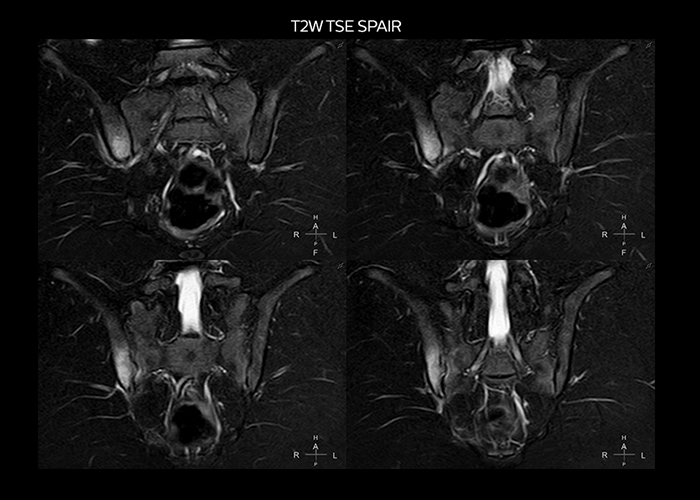

“On average, we scan about 80 patients per day, but on some days we scan well over 100 patients. The scanner is in use 7 days per week, operated 20 hours per day on week days and 8 hours per day in the weekend,” Mr. Tuna says. “To avoid coil changes we plan examinations of similar anatomies back to back, such as head and spine. Multiva helps us here a lot because coils don’t need to be changed frequently. Moreover, thanks to parallel imaging technology and 16-channel HeadSpineTorso and 8-channel MSK coils we are able to achieve excellent image quality. In this way Multiva helped us to increase both image quality and productivity.” “Neurological cases, such as brain and spine imaging, represent the largest share in our MR scanning, followed by musculoskeletal cases. In general, we use simple and basic imaging protocols. But occasionally, we use advanced techniques for problematic cases if necessary.

“Since we have Multiva, we have improved our workflow, because it has been so easy for our operators to learn and use Multiva. Our operators notice that the coils are lightweight and coils don’t need to be changed frequently. The user interface is easy to use. Features like this help us to scan a high number of patients. For instance, the musculoskeletal coils can be used interchangeably, and due to the user-friendly interface, the number of mistakes such as, for example, correct coil element selection has decreased significantly, because the system does it automatically by itself.” “Most important, Multiva satisfies our clinical imaging needs very well,” says Mr. Tuna. “Many features of Multiva have become similar to the Ingenia system. Even in more complex imaging such as abdominal and cardiac, the image quality and performance of Multiva is better than we expected. General surgeons and physicians from our hospital’s internal medicine department prefer to refer to us because of this.”